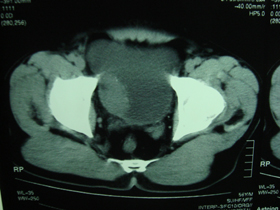

典型病例,男,56岁。无痛性血尿3月。

膀胱占位性病变,呈菜花状生长,考虑膀胱癌。 期待病理。